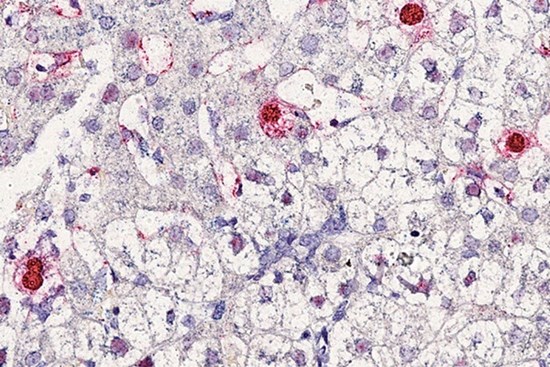

Các nhà khoa học phát hiện loại virus tuần hoàn mới, có tên là circovirus 1 (HCirV-1), gây bệnh viêm gan ở người.